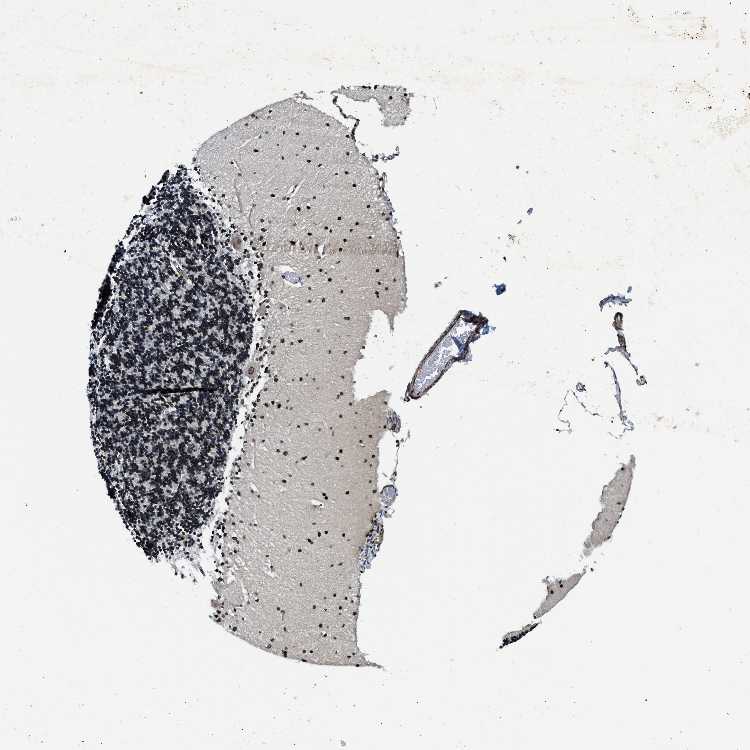

CEREBELLUM - Antibody stainingi

Antibody staining in the annotated cell types in the current human tissue is reported as not detected, low, medium, or high, based on conventional immunohistochemistry profiling in selected tissues. This score is based on the combination of the staining intensity and fraction of stained cells.

Each image is clickable and will lead to virtual microscopy that enables deeper exploration of all samples and also displays staining intensity scores, fraction scores and subcellular localization as well as patient and tissue information for each sample.

Antibody HPA019089Antibody HPA024023

Purkinje cells MediumHigh

Cells in granular layer MediumHigh

Cells in molecular layer HighHigh